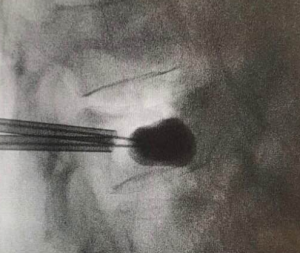

Vertebroplasty is a minimally invasive operation with a pinhole, injecting artificial bone powder (acrylic adhesive) into the vertebral body. Vertebroplasty was completed with fractures of the 12th thoracic spine and the 3rd lumbar spine